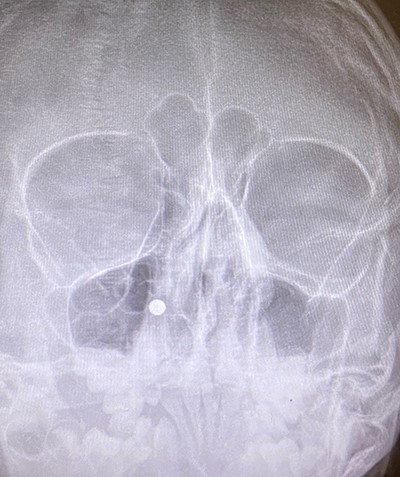

An 11 year-old male was transferred to the emergency room after being shot with a BB gun while playing. The patient’s custodian reports that he returned home with severe bleeding from bilateral nostrils which spontaneously resolved. The patient denies postnasal drip or salty taste. His medical history includes bipolar disorder and attention-deficit disorder managed with medications. On physical examination, an entry point wound is noticed in the skin of the left nasal sidewall (Figs 1 and 2). No active bleeding is noticed from anterior nasoscopy or in the posterior oropharynx exam. The rest of the head and neck examination is unremarkable. Plain X-rays performed in the emergency room confirm the presence of a metallic object in the right nasal cavity/paranasal sinuses (Figs 3 and 4). After consent is obtained, the patient is taken to the operating room and nasal endoscopy is performed. The left nasal cavity appears unremarkable. In the posterior nasal cavity, minimal bleeding and avulsed tissue is noticed after medialization of the middle turbinate. After minimal removal of tissue with pediatric Blakesley forceps, the BB bullet is visualized as lodged in the right posterior nasal cavity adjacent to the posterior attachment of the middle turbinate (Fig. 5). The bullet was then grasped with Takahashi forceps and removed after minimal endoscopic dissection (Fig. 6). Following extubation, the patient was observed for 8 h prior to discharge. During this period, no signs of recurrent epistaxis or cerebrospinal fluid rhinorrea were noticed.

In the past, non-powder guns were traditionally spring-loaded weapons that would release their projectile at a muzzle velocity (the speed of a projectile the moment it discharges from the muzzle of a gun) at less than 350 feet per second (fps). Recent advances in compressed-gas technology have increased muzzle velocities of non-powder guns to 900–1200 fps, which approximates the muzzle velocities of modern rifles with high-velocity cartridges [3]. Case series of penetrating injuries in the head and neck caused by BB and pellet guns have been previously reported [4, 5], but there are only two reports of similar injuries with BB guns in the paranasal sinuses [6, 7]. The path of the bullet is pertinent to the unusual presentation in our case: the entry point of the bullet was observed in the skin of left nasal sidewall at the level of left upper cartilage, and plain X-ray film showed the metallic bullet was located in the right nasal cavity. In the initial evaluation under the emergency situation, this raised concerns for a laterality error and mirroring of the plain X-ray image. This was readily addressed after discussion with the radiology technicians to confirm the imaging protocol was correct. After a thorough discussion of the procedure, the patient’s custodian consented to bilateral nasal endoscopy and need for possible bilateral intervention prior to proceeding to the operating room.